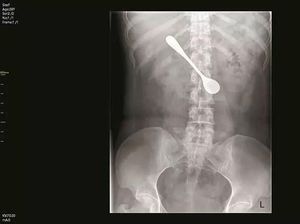

Nasib malang menimpa seorang wanita di China. Di tenggorokannya bersarang sendok berukuran 13 cm gara-gara ia ingin mengambil tulang ikan yang nyangkut!